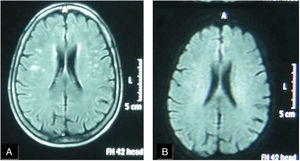

A female patient aged (27 years) and suffered from SS since (3 years). (A) FLAIR MRI shows a rather-defined single hyperintense signal lesion seen at deep periventricular white matter of the parietal regions with no comparable signal abnormality on DWI (B) suggesting late subacute to chronic ischemic lesions.

Six patients (40%) showed brain lesions using FLAIR MRI (in different supratentorial deep and subcortical brain regions (Table 2, Figs. 1 and 2). Three (20%) of them had severe peripheral vascular affection, while each of the remaining patients had mild, moderate or no peripheral vascular affection. Diffusion weighted MRI failed to detect any hypo- nor hyper-intense lesions (Table 2). A non-significant relation (P=.259) between the presence of WMH lesions and the severity of peripheral vascular affection of the disease (Medsgar Vascular Score) (Fig. 3), as well as non-significant strong correlation was found (r=0.085, P=.764) was also observed.